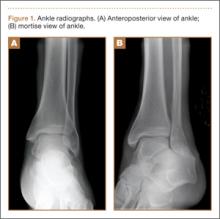

An increasingly common injury among snowboarders is a fracture of the lateral process of the talus; this injury accounts for 32% of snowboarders’ ankle fractures.6 The lateral process of the talus—wedge-shaped and covered in articular cartilage—is involved in the subtalar and ankle joints.9 A fracture here is often misdiagnosed as an ankle sprain (Figures 1–3).6,9,10 The exact mechanism of injury remains controversial, and several biomechanical factors seem to be involved. Funk and colleagues11 conducted a cadaveric study and concluded that eversion of an axially loaded, dorsiflexed ankle may be the primary injury mechanism for fracture. Furthermore, snowboarders have their feet in a position perpendicular to the board, and a fall parallel to the board could increase the eversion force on the ankle of the leading leg. Valderrabano and colleagues9 conducted a clinical study of 26 patients who sustained this injury from snowboarding. All the patients reported they had felt an axial impact from falling, jumping, or unexpectedly hitting a ground object, and 80% reported a rotational movement in the lower leg during the impact. The authors concluded that axial loading and dorsiflexion were not the only factors involved in lateral process talus fractures, and an external moment is necessary to cause this injury from a forward fall.9